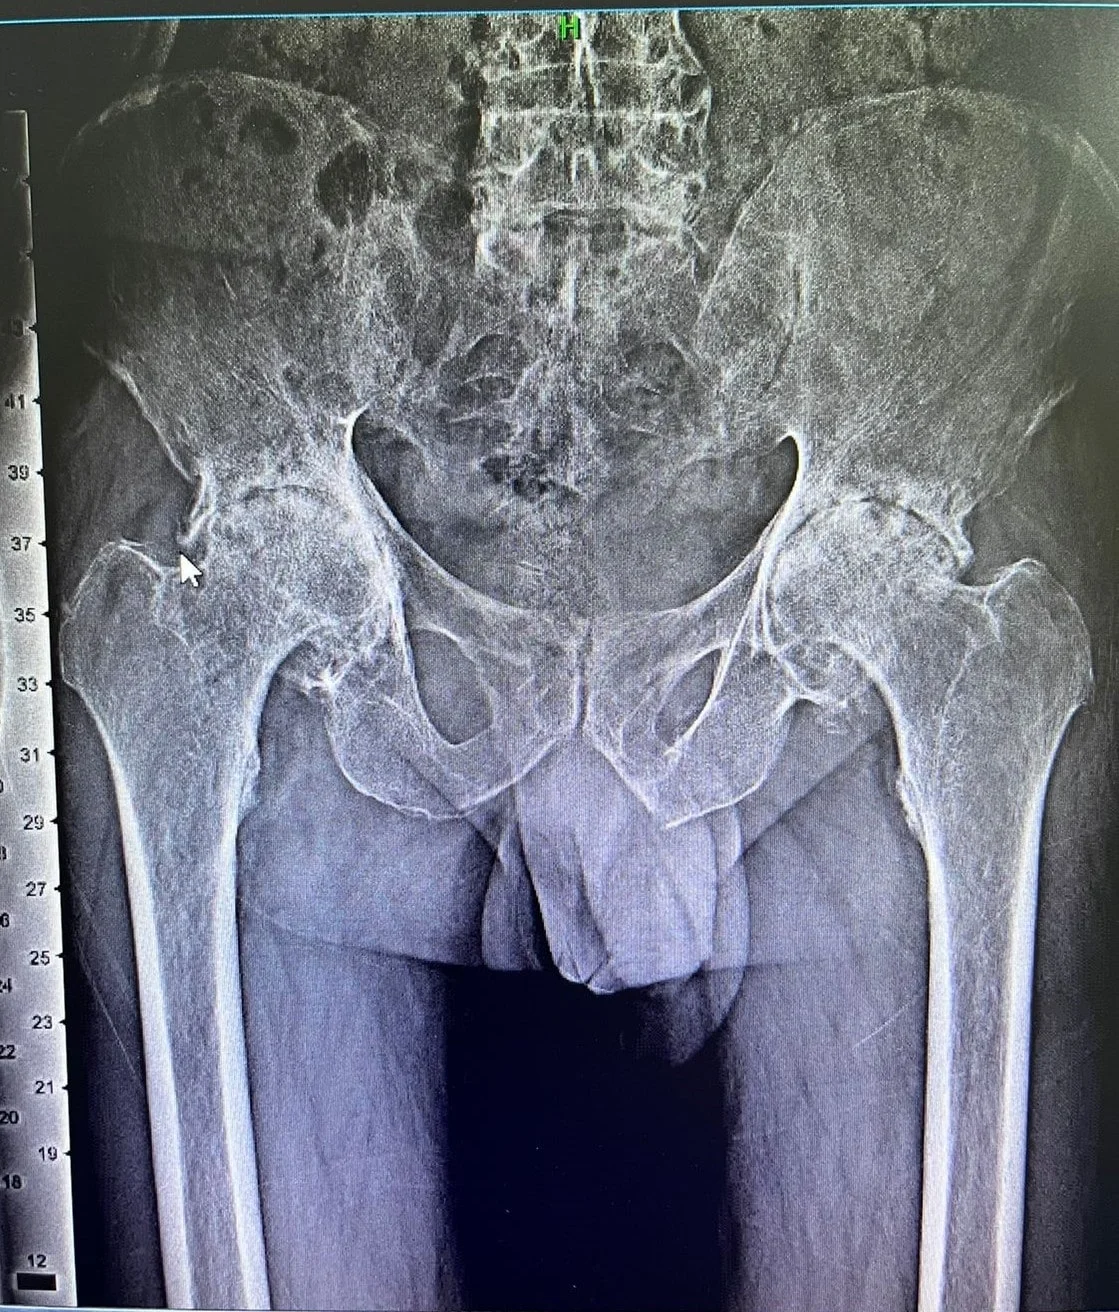

3. Osteoarthritis:

By far the commonest indication of Total Hip Replacement. Essentially due to degeneration of articular cartilage of the hip joint resulting from age related or secondary to any hip pathology.

4. Inflammatory Arthritis:

Genetically predisposed autoimmune disorders like Ankylosing Spondylitis, Rheumatoid Arthritis causes inflammation of the hip joints with consequent arthritis & osteoporosis. Eventually the progression of disease results in significant pain, stiffness & incapacitation of day-to-day activity thus necessitating Total Hip Replacement.

5. Developmental Dysplasia:

Essentially a developmental anomaly with distortion of normal hip anatomy leading to premature hip arthritis with shortening & instability. Often an indication of Complex Primary Total Hip Replacement in relatively younger population.